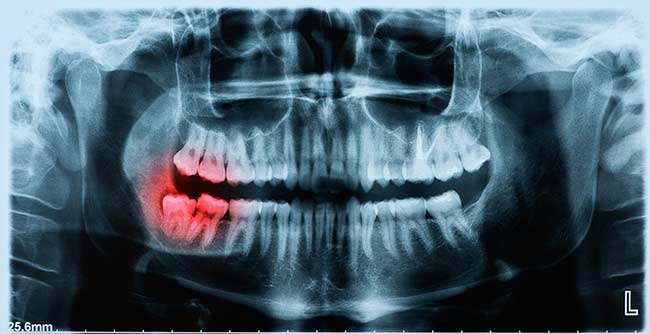

wisdom-teeth-removal-xray

Before surgery begins, you can take part in a consultation to ensure the right treatment is being offered. You will be given a local anaesthetic on the day of the removal to numb the area and may also need a general anaesthetic if multiple teeth are being extracted. Your surgeon will open up gum tissue near the tooth and remove any hone over it before extracting the tooth. They may need to cut the tooth into small pieces to extract it. Wisdom tooth removal is likely to be easier if the tooth has fully erupted, but the process may be more complex if the only partial eruption has occurred. In any case, wisdom tooth removal can help you avoid tooth decay, lift you out of pain and give you a straighter bite.

Not everyone has to have their wisdom teeth removed, but many people have no choice but to take action. If your wisdom teeth don’t fit in your mouth adequately, you may wish to get in touch. Wisdom teeth can erupt if you don’t have enough room for them. Teeth can start to erupt once you obtain more than 28 teeth. Taking action can mean avoiding additional complications in the jaw. You may also wish to seek help if you have been experiencing pain in the gums around your wisdom teeth. Food and bacteria can often become trapped around the wisdom teeth, causing infections. Taking the teeth out can help you avoid subsequent infection.

Oral surgery may also be the solution if wisdom teeth have forced other teeth to slide out of alignment. If you no longer have straight teeth because of eruption, we can help. Wisdom teeth can also be difficult to clean and therefore cause other teeth to decay. Removal can help you overcome a variety of problems related to wisdom teeth.